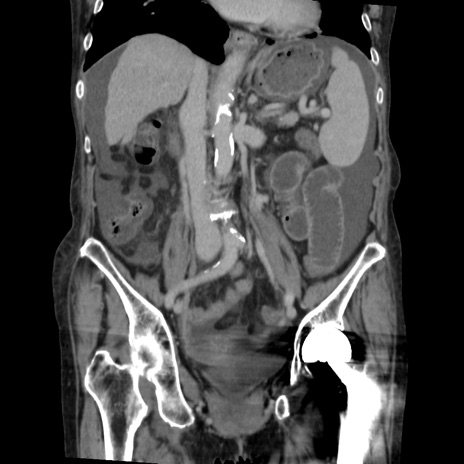

症例31(冠状断像)

【症例】80歳代 女性

【主訴】腹部膨満感

【現病歴】他院にて肝硬変にてフォロー中。1週間前から便秘、腹部膨満感、臍部腫瘤あり受診となる。

【既往歴】肝硬変

【身体所見】腹部膨隆あり、皮膚変化なし、疼痛なし。

【データ】WBC 4600、CRP 0.25